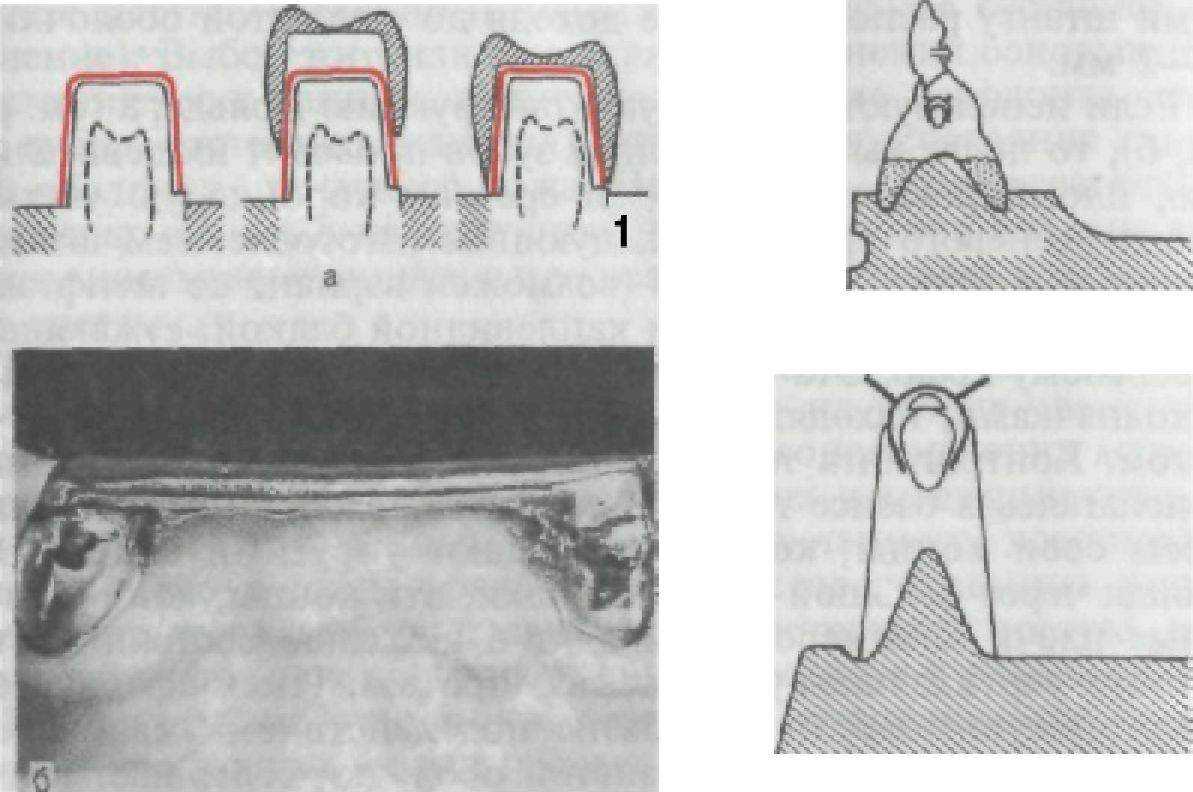

Рис. 128. Конструкция телескопической коронки (а) и штанговая конструкция Румпеля (б) и Дольдера (в).

Другой разновидностью телескопической системы фиксации является штанговая или балочная система. Эта конструкция включает в себя опорную несъемную часть в виде коронок или надкорневых колпачков, между которыми имеется штанга или балка; соответственно в базисе располагается металлическая контрштанга, точно повторяющая форму штанги. Штанга Румпеля — прямоугольная плоская, а штанга Дольдера — каплевидная (рис. 128), за счет чего происходит надежная фиксация и стабилизация протеза через соответствующую контрштангу, имеющую лишь одну степень свободы движения — вертикальную, совпадающую с осью опорных зубов. Применение этой конструкции рекомендуется при таких дефектах, когда между опорными зубами альвеолярный гребень прямолиейный или приближен к этой форме. При дугообразом альвеолярном гребне через штангу на опорных зубах при откусывании или разжевывании пищи возникает рычагообразный наклоняющий момент, отрицательно сказывающийся на состоянии пародонта. Опорные зубы при румпелевской системе должны быть достаточно высокими, позволяющими штангу расположить не доходя до слизистой оболочки на.

Если используют штанговую конструкцию Дольдера (см. рис.

128, б), то после выбора опорных зубов проводят их девитализацию, пломбирование каналов и срезают коронковую часть до уровня десневого края с последующим изготовлением штампованных или литых колпачков (возможен вариант со штифтами), соединенных яйцевидной или каплевидной балкой, сужающейся к десневому краю. Эта опорная балка может располагаться между колпачками, находящимися на расстоянии или рядом друг с другом. Контрштанга точно повторяет форму опорной части и, располагаясь в базисе протеза, сохраняет свободными от пластмассы свои концы, которые обладают упругими свойствами. Пройдя через большой диаметр балки, эти концы, какретенционные плечи кламмеров, приходят в исходное состояние, препятствуя вертикальному смещению протеза. Имея сферическую конгруэнтную поверхность, базис под действием жевательного давления и податливости слизистой оболочки совершает вращательное движение вокруг оси балки, не создавая отрицательных боковых нагрузок на пародонт опорных зубов. Система Дольдера показана преимущественно при изготовлении протезов на нижнюю челюсть. Она расширяет показания к сохранению и корней зубов, так как фиксация и стабилизация протезов на нижней челюсти при полном отсутствии зубов остается трудноразрешимой проблемой. И в той, и в другой конструкциях необходимо предусмотреть сохранение зазора 0,2—0,3 мм между штангой и контрштангой в спокойном положении протеза на челюсти с учетом погружения базисов в слизистую оболочку протезного ложа.